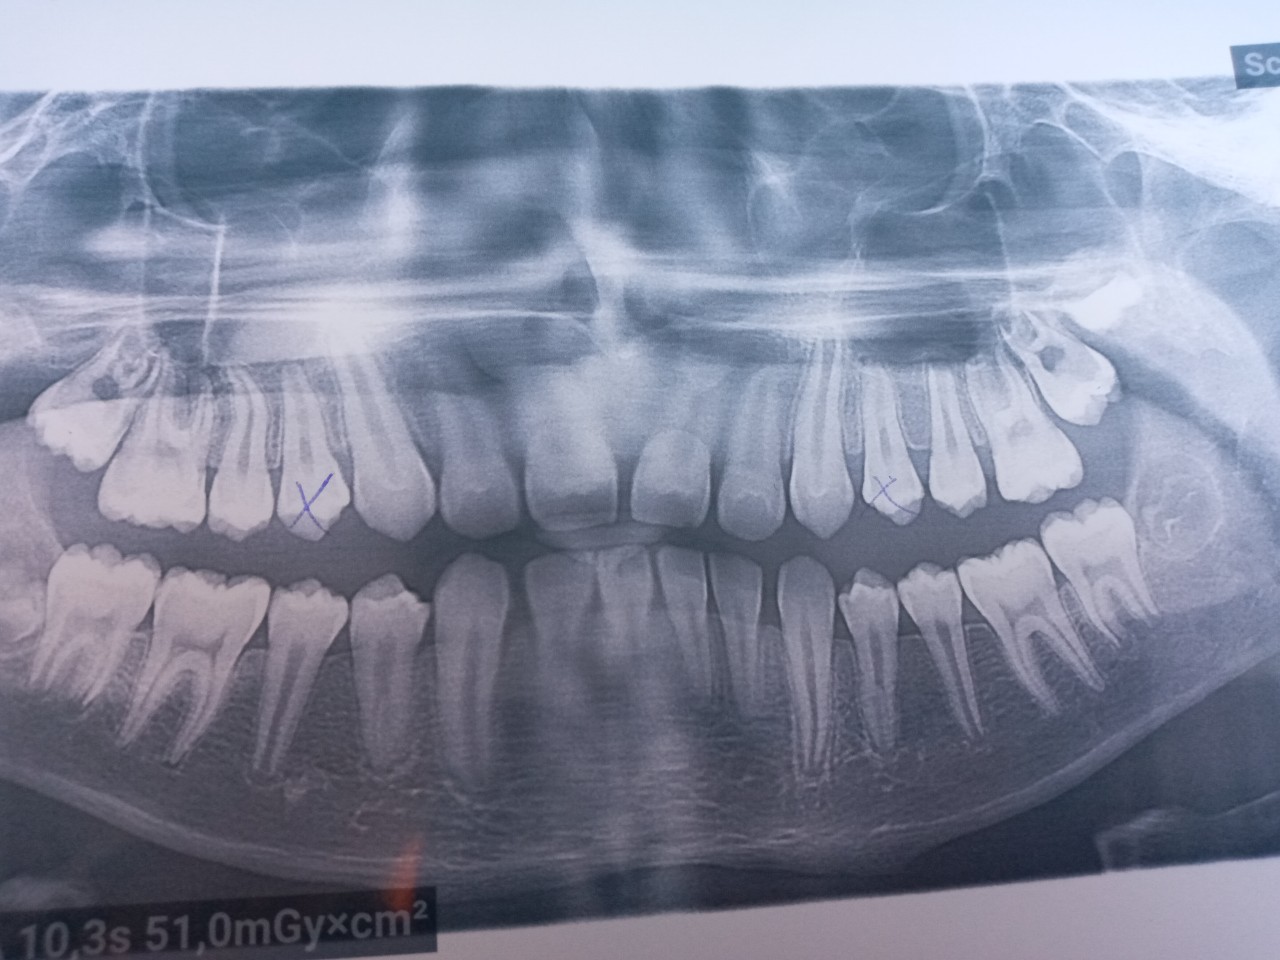

Фотографии и схемы для ОПТГ и мезиального прикуса